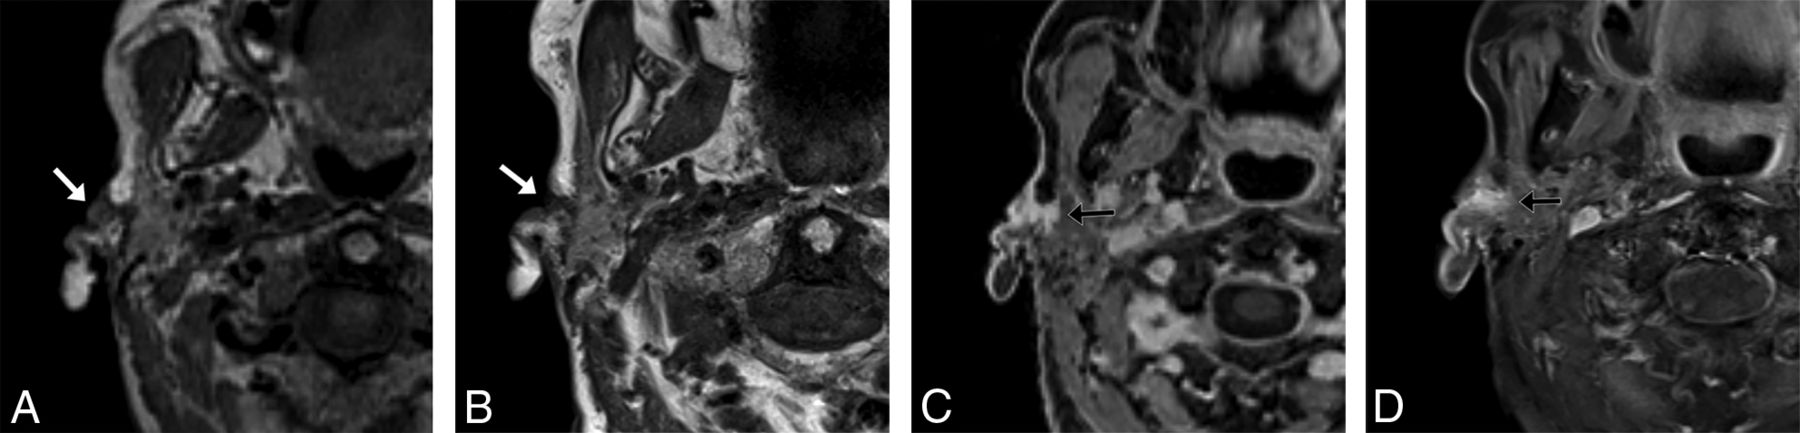

During our optimization phase, we tested submillimeter coronal acquisitions in our sinus protocol, similar to our high-resolution axial protocol for the nasopharynx and oropharynx. We show an example of perineural tumor from one of these examinations in an 85-year-old man with a spindle cell sarcoma in Fig 6.

An 85-year-old man with spindle cell sarcoma with sinus protocol MR imaging. T1 VIBE Dixon axial acquisition performed with 0.9-mm3 (0.74 mm isotropic) voxels clearly shows tumor (arrows) along the left V2 (A) and in the left lateral cavernous sinus wall (B), neither of which is clearly seen on the 2D T1-weighted images (C and D) with spectral fat suppression with 2-mm3 (4 × 0.7 × 0.7 mm) voxels. The 3D examination shown was performed on a 3T Magnetom Prisma Fit system (Siemens) 3 weeks before the 2D examination, which was performed on a Siemens 3T Vida system, with no intervening treatment.